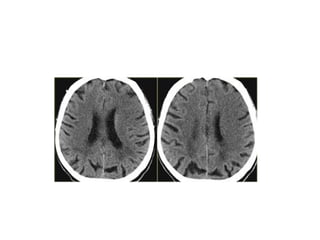

CT SIGNS

1.Hypoattenuating brain tissue

• The diagnosis is infarction, because of the

location (vascular territory of the middle

cerebral artery (MCA) and because of the

involvement of gray and white matter,

which is also very typical for infarction.

2.Obscuration of the lentiform

nucleus

• Obscuration of the lentiform nucleus, also

called blurred basal ganglia, is an

important sign of infarction.

It is seen in middle cerebral artery

infarction and is one of the earliest and

most frequently seen signs.